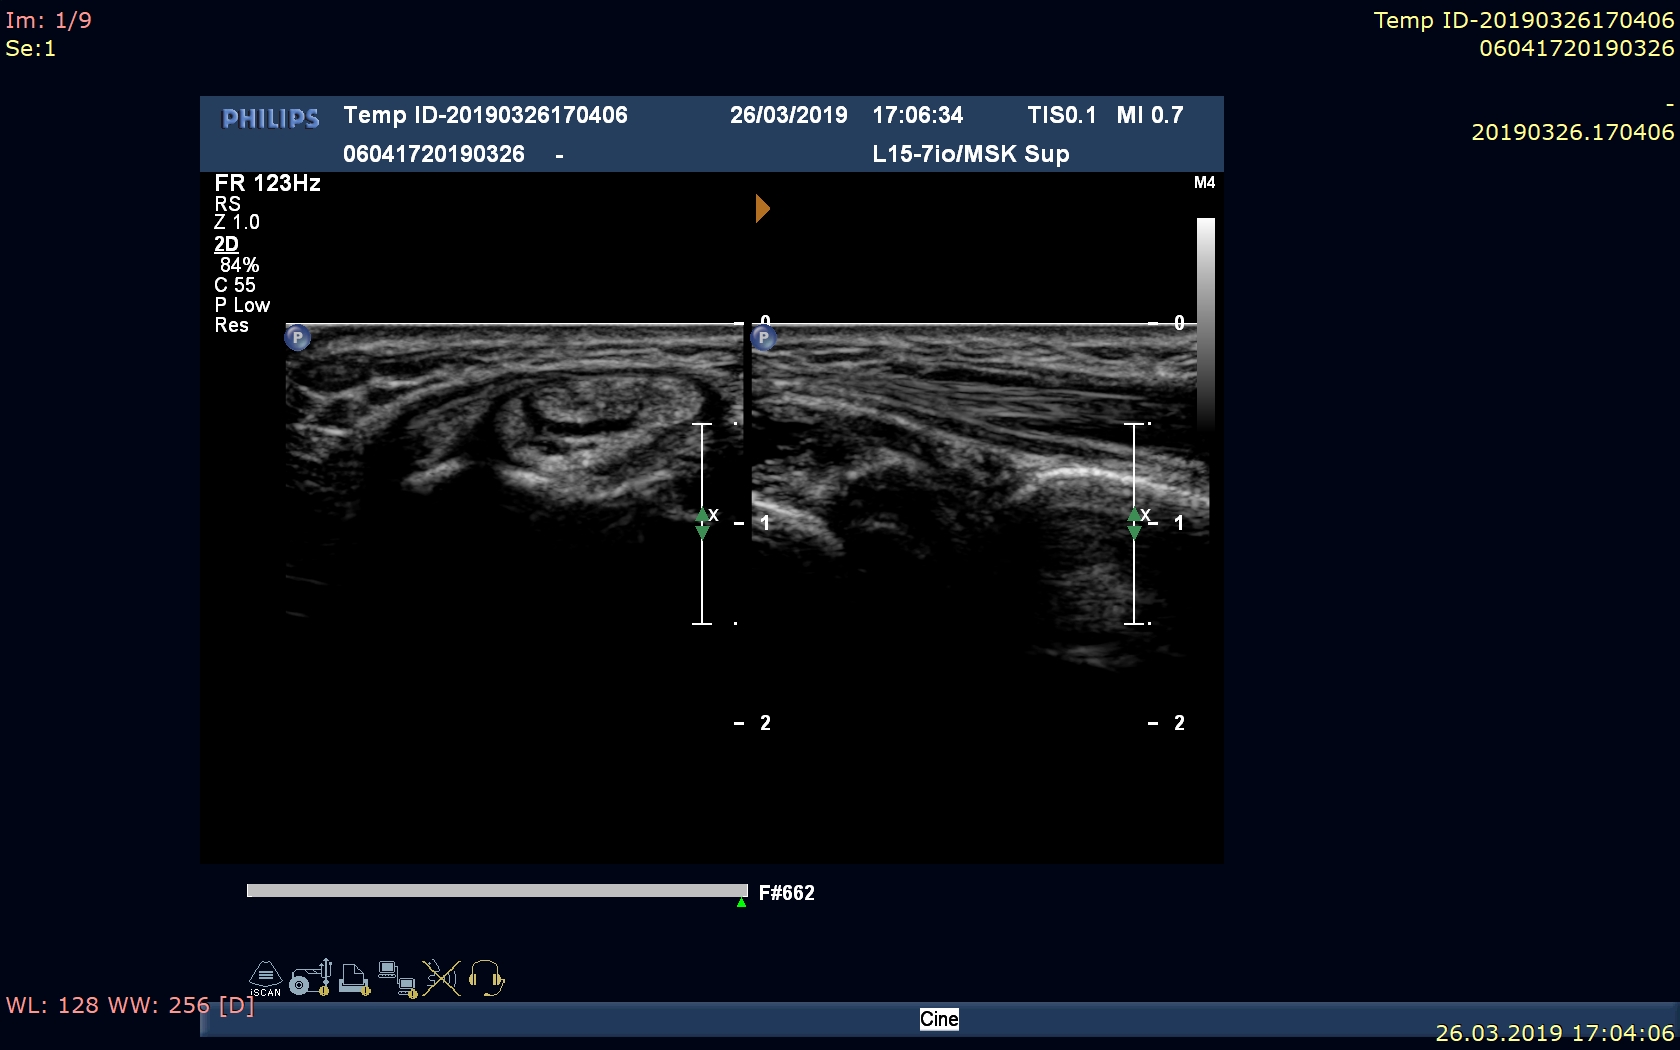

Pacjent po urazie w mechanizmie upadku – przebyte złamanie nadkłykcia bocznego